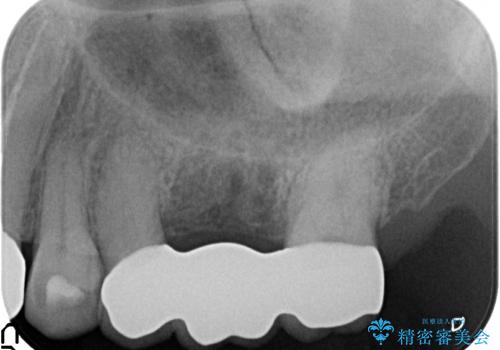

- 左上6番目の歯が疼くので診て欲しいといらっしゃった方の症例です。

左上6のクラウン及びコアを除去したところ、歯根が破折していたため抜歯し、ブリッジによる補綴を行いました。

今回用いたオールセラミッククラウンは、ジルコニアフレームという白い素材の上にセラミックを盛っているため審美性が非常に高いのが特徴です。

またジルコニアは人工ダイヤモンドの材料にも使われているほど高い強度を持っており、そのためオールセラミッククラウンは審美性だけでなく、奥歯やブリッジの補綴も可能とするクラウンです。